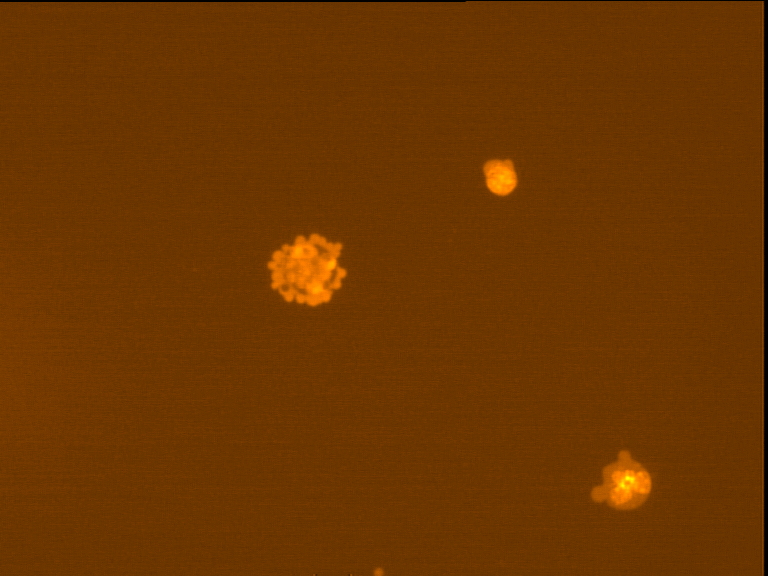

Fig. 4 through 6 show the morphological features of Raji cell sub-lines exposed to DOX, indomethacin, or verapamil. Some of the reversal agents significantly increased the frequency of apoptotic cells compared with control cells. Thus, the P-gp reversal agents were able to overcome apoptotic resistance in the NHL cell-line model. Apoptotic cells in the controls contributed approximately 10% of the whole population (i. e., 61/600 x 100 = 10.16% for TK+ and 69/600 x 100 = 11.5% for TK-). After exposure to the P-gp reversal agents, apoptic cells increased to 22.3% with indomethacin and to 43% with doxorubicin in TK+ cells. In TK- cells, apoptic cells increased from 11.5% to 26.8% and 75.7% with indomethacin and doxorubicin, respectively.

Fig. 4: Comet images of the Raji cell sub-lines after treatment with 25 nM DOX for 48 hours in 37°C and 5% CO2. TK+ treated cells (left). And TK- treated cells (right), as photographed with the Leica microscope below X 200

Fig. 5: Morphological features of Raji TK+ cells after treatment with indomethacin (1), verapamil (2) and DOX (3). In each row, left images show intact cells, middle images show apoptotic cells, and right images show necrotic cells as they appeared under the microscope X 200